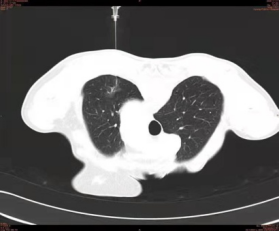

患者,男,70岁,体检时无意中发现左肺上叶磨玻璃密度灶,病灶范围约3CM左右,恶性表现明显。经多学科会诊,建议手术切除。

17日上午,影像科副主任马亮为患者进行术前定位。先行胸部CT扫描,固定患者体位,确定进针点,测量进针深度及角度,局麻后用肺结节定位针缓缓刺入肺组织中,到达病灶下界边缘后留置,CT再次扫描证实针尖位置与术前计划一致,拔出针芯,释放定位钩,推送定位线至胸壁内。术毕即刻送患者到手术室成功进行了胸腔镜下切除术。